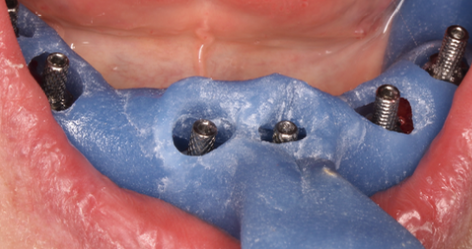

Proteza este realizată de către tehnicianul dentar care utilizează o copie din gips a arcadelor dentare (Fig. 3.9.6 și Fig. 3.9.7) în care va poziționa replici ale implanturilor. Poziționarea acestor replici se face pe baza unei amprente. Aceasta se ia cu ajutorului unui suport personalizat fiecărui caz numit „portamprentă individuală” (Fig. 3.9.9) în care se plasează un material de amprentă.

Pentru a transmite laboratorului de tehnică dentară poziția exactă a implanturilor dentare se folosesc dispozitive speciale, numite bonturi de transfer, care se înșurubează în implant. Acestea vor rămâne prinse/fixate în materialul de amprentă. Pentru a ne asigura că rămân perfect paralele și nu-și modifică deloc poziția în materialul de amprentă, ele se solidarizează. (Fig. 3.9.8)